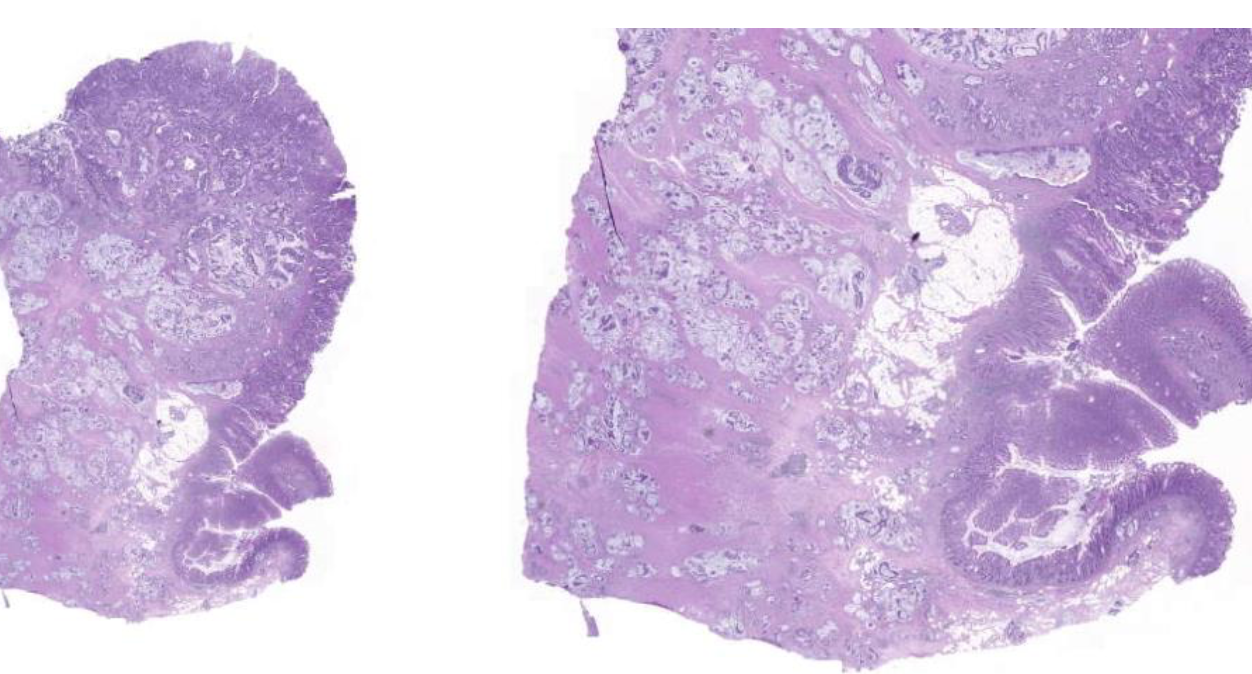

Diagnose?

Adenokarzinom des gastroösophagealen Übergangs = Barettkarzinom

Viel häufiger als Plattenepithel-CA, wird immer irregulärer je höhergradig und tieferreichender der Tumor ist, Dysplasie ist Vorstufe und Notwendigkeit zur Therapie